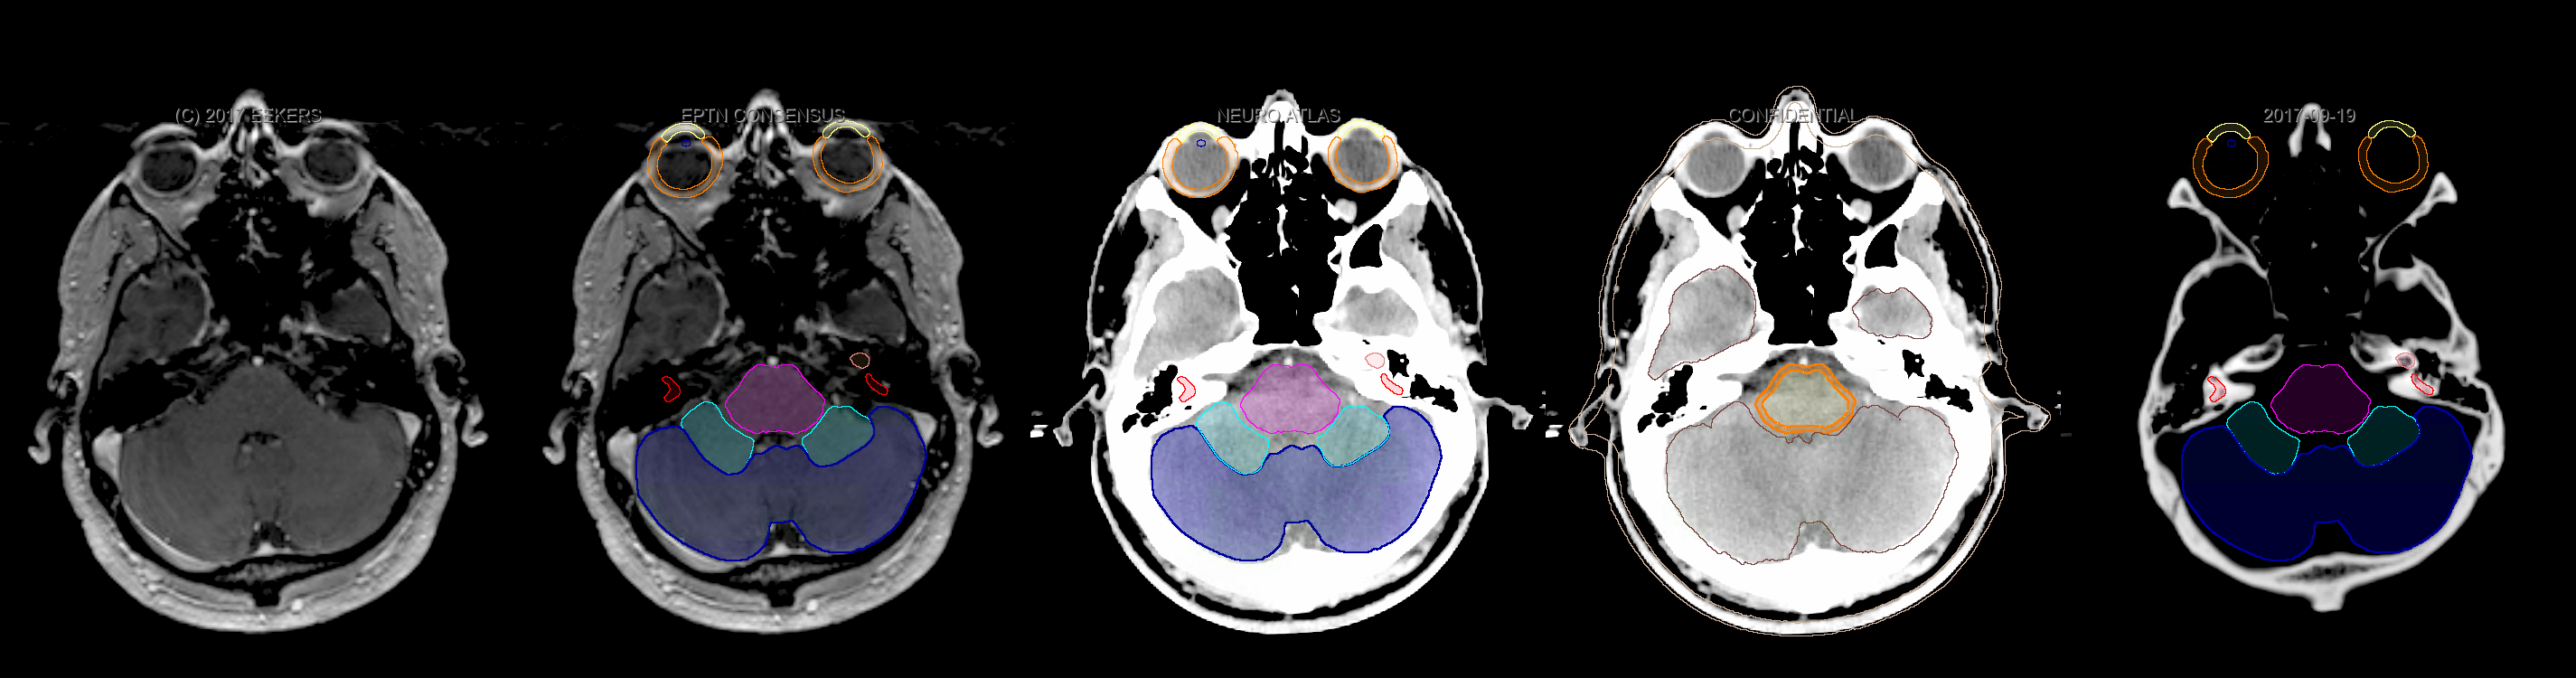

Three-dimensional delineation of the fifteen consensus OARs for neuro-oncology are shown on CT and 3 Tesla (3T) MR images (slice thickness 1 mm with intravenous contrast agent). All are presented in transversal, sagittal and coronal view.

From left to right: MR without structures, MR with structures, CT (WW/WL 120/40) with structures, CT (WW/WL 120/40) with Brain and Brainstem Surface, CT (WW/WL 1500/120)with structures